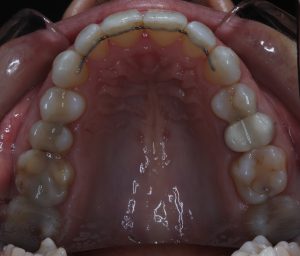

INTENSIVE

52 Semanas de tratamiento